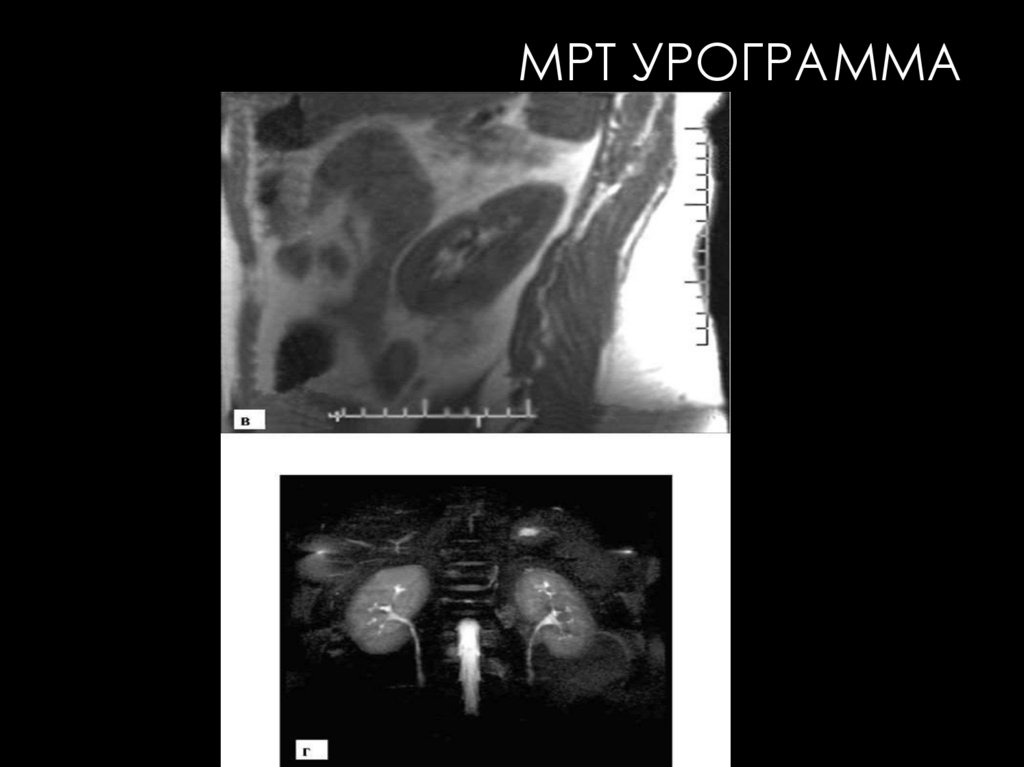

МРТ УРОГРАММА

МРТ

Современные высокопольные МР-томографы обладают большими

возможностями визуализации и детальной характеристики всех

мочевых органов. Базовой методикой исследования мочевых

органов является нативная МРТ.

Возможности МРТ в диагностике заболеваний мочевых органов

значительно расширяются при использовании специальных

методик:

•МРТ с контрастным усилением

•МР-ангиография

•перфузионная МРТ.

•магнитно-резонансная

урография (МР-урография)